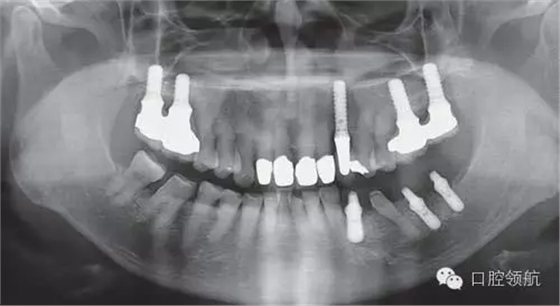

利用曲面斷層及CBCT檢查埋入部位情況,雖未出現(xiàn)與主訴相關的神經損傷,但無意中卻發(fā)現(xiàn)了種植體的舌側穿孔(圖1、圖2)。

圖1 術后的曲面斷層影像。